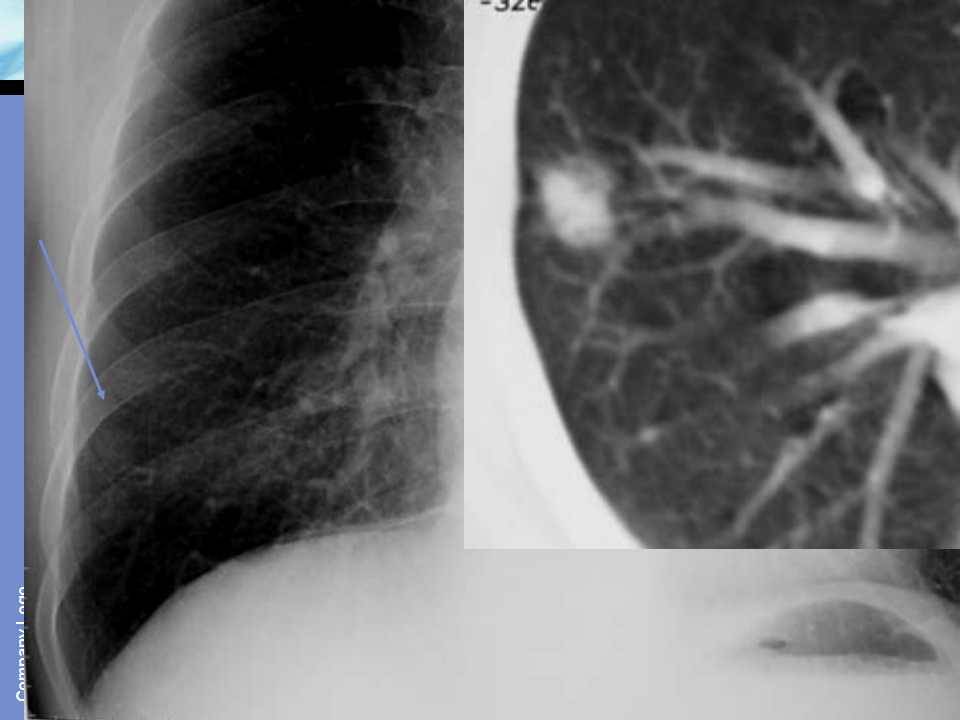

肺癌影像诊断